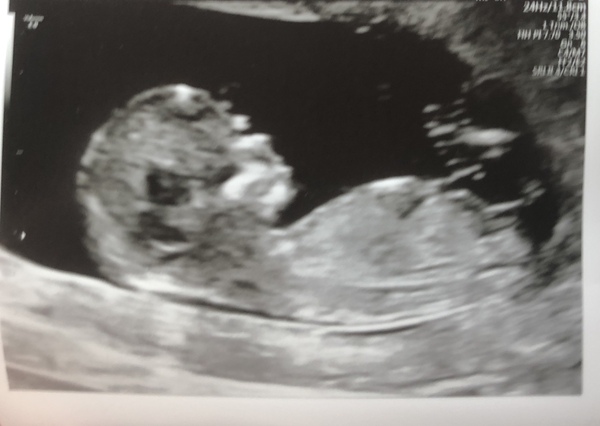

Hi there, just had my scan (to check if my bleed has settled down, which it has)

I had a very bouncy baby- wouldn't stop moving. Measured ahead again at 11weeks exactly. So EDD July 24th. So very happy and so reassured now.

I know it's super early but I really think I'm having a boy. Placenta is on the right hand side.

I'm so happy I could cry. Xx